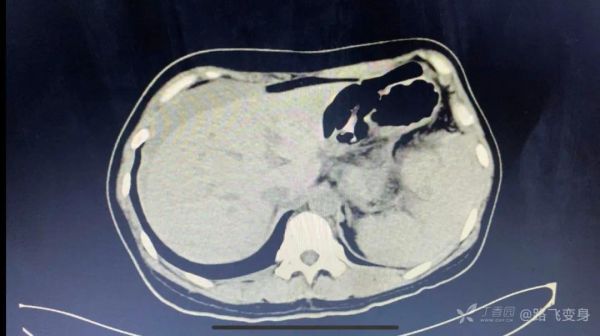

病人出现「休克」症状,没有办法只有准备手术,术前常规行全腹部 CT 检查,如下:

CT 发现明显异常。可以和下面第一次急诊 CT 视频做对比。

丁香园站友 @旧故里草木生 认为:两张片子对比,最明显的改变是脾脏周围有异常混杂密度影,肝周积液,又是个育龄期女性,大胆猜测脾脏异位妊娠导致的破裂。

丁香园站友 @zhangzihua87 认为:腹腔出血伴休克是没有疑问的。第一次 CT 脾门附近可疑软组织密度,第二次 CT 肝周积液,脾门软组织密度增大、不均,考虑破裂。一般考虑脾门血管瘤破裂。与妇科手术有关的话,大胆推测子宫内膜异位破裂。